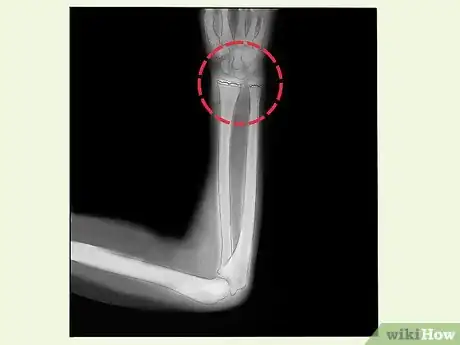

4Get imaging tests. In addition to your exam, your doctor may order imaging tests. X-rays or an MRI can give the doctor a better idea of the fracture. They can also help determine the best treatment for you.[8]

5Have your fracture fixed. Following your exam and an X-ray or MRI, your doctor will let you know if you have a growth plate fracture. The treatment to fix the fracture will depend on its severity. Fractures that are less severe may need a cast or splint. You may require surgery for more serious fractures. Each treatment helps the growth plate and bone heal properly. This can prevent permanent damage or deformity.[9]

- You may need surgery if the break is unstable or your bone fragments are displaced. Surgery generally sets the bones in place with screws, wires, or metal plates.[10]